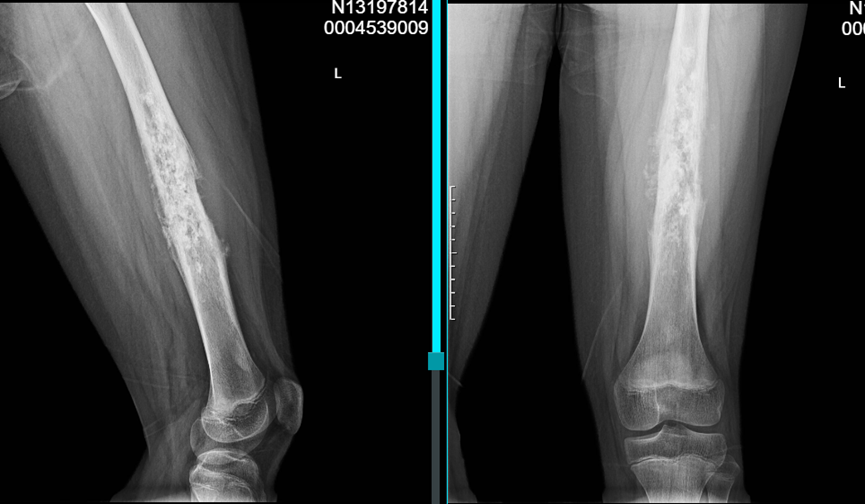

患儿,12岁,活泼好动的男孩,因"左大腿疼痛2个月,加重伴肿胀1周"来我院就诊。起初家长以为只是生长痛或运动损伤,直到疼痛日益加重并出现局部肿胀才引起重视。